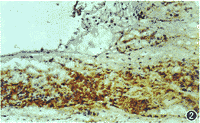

HLA-DR和ICAM-1的阳性表达部位为细胞膜。正常角膜中2例HLA-DR和ICAM-1轻度表达,并且阳性细胞均位于近角巩膜缘上皮基底细胞。病变角膜,尤其是炎性病变、移植排斥反应、化学损伤以及有新生血管伸入的角膜白斑,HLA-DR和ICAM-1阳性细胞增多,可表达于角膜上皮细胞、内皮细胞、基质细胞、巨噬细胞、树突状细胞和淋巴细胞表面(表1,图1,2)。正常角膜和各类病变角膜的HLA-DR、ICAM-1及其两者共同表达的阳性率差异有显著性(P<0.01)。

图2 角膜溃疡周围及底部有大量炎性细胞浸润,细胞膜明显着色 SP×20